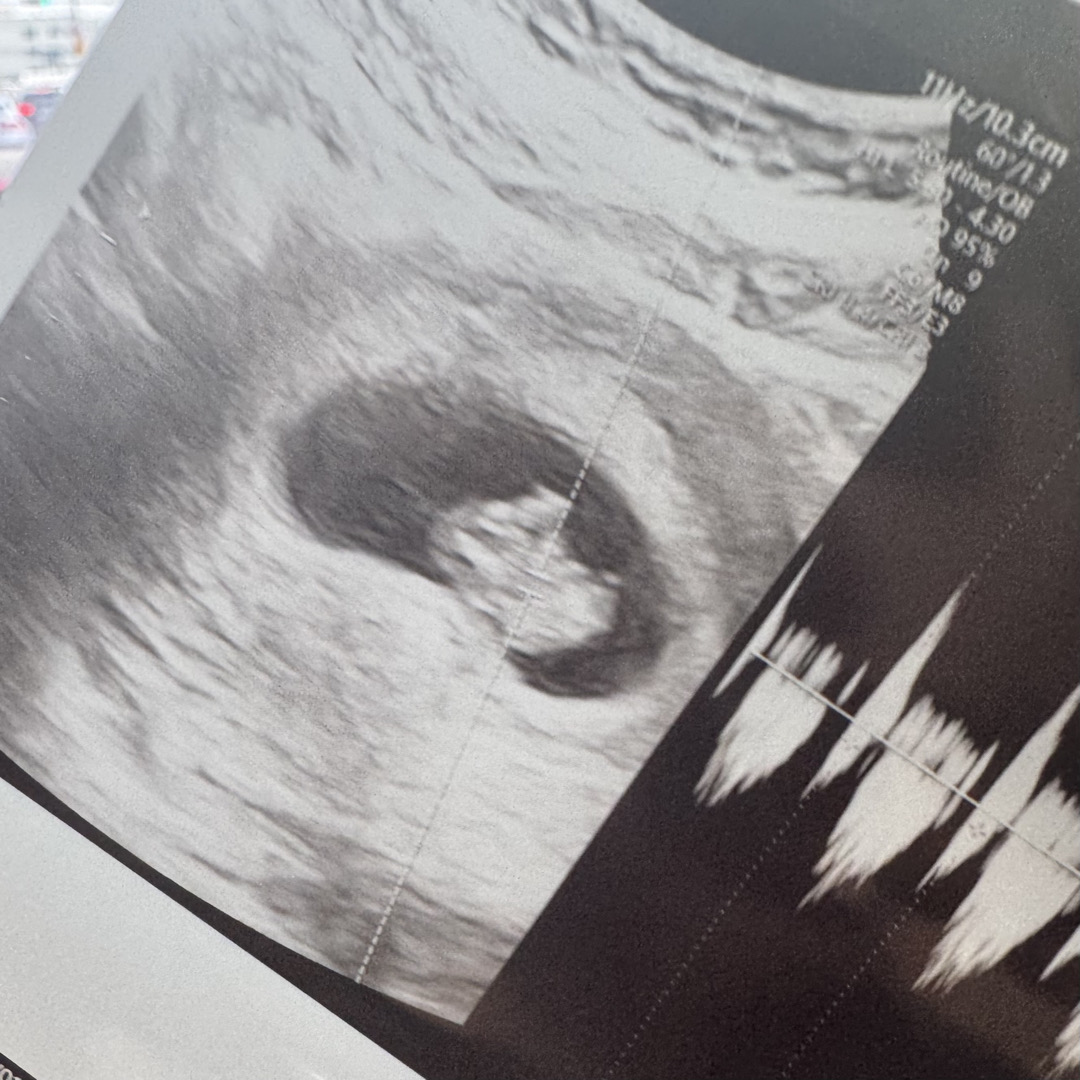

8주2일 입니다 !

초음파보면 이시기에는 움직임이 없나요? ㅎㅎ 통닭 모양 입니다. 탯줄은 연결되어있는데 가만히 있어용 ㅎㅎ

마쟈요 3일만에 갔는데 0.3cm 더 컸더라구용 ,,,!!?ㅋㅋㅋㅋ 8주면 아딕 움직이지 않는거죵? ㅎㅎ 별게 다 불안한 초보예비맘이네요,, 😂